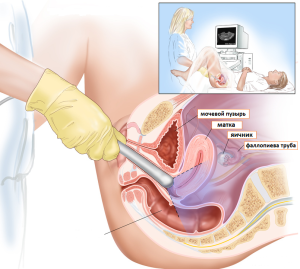

Пацієнтці необхідно зняти весь одяг нижче пояса, після чого лягти на спину на кушетку, зігнувши ноги в колінах.

Дослідження проводиться трансвагинально, тому лікар спочатку одягає на датчик презерватив, а вже після цього вводить його в тіло. Далі за допомогою приладу лікар сканує репродуктивну систему, в тому числі матку і плодове яйце.

У другому і третьому триместрі діагност вже оцінює стан всіх систем ембріона, а також у зв'язку з протипоказаннями до трансвагінальний дослідженню проводиться доплерографія або обстеження через черевну стінку.

Ще одним методом видалення завмерлого ембріона стає вакуумна аспірація, її застосування можливо на ранніх (до 15 тижні) терміни. Цей метод має досить переваг: його можна проводити в амбулаторних умовах, для такої аспірації потрібно менше медикаментів і знеболюючих засобів, також вона не погіршує прогноз для подальшого зачаття. Проводиться такий аборт шляхом вилучення плодового яйця з маткової області при використанні спеціального вакуумного апарату (без вискоблювання): при цьому особливий катетер вводять всередину навіть і завдяки створюваному рівномірному тиску яйце виходить назовні. Міні-аборт може займати не більше 10 хвилин і поки є найкращим способом переривання вагітності при завмерлому плоді.

Схема вакуумної аспірації